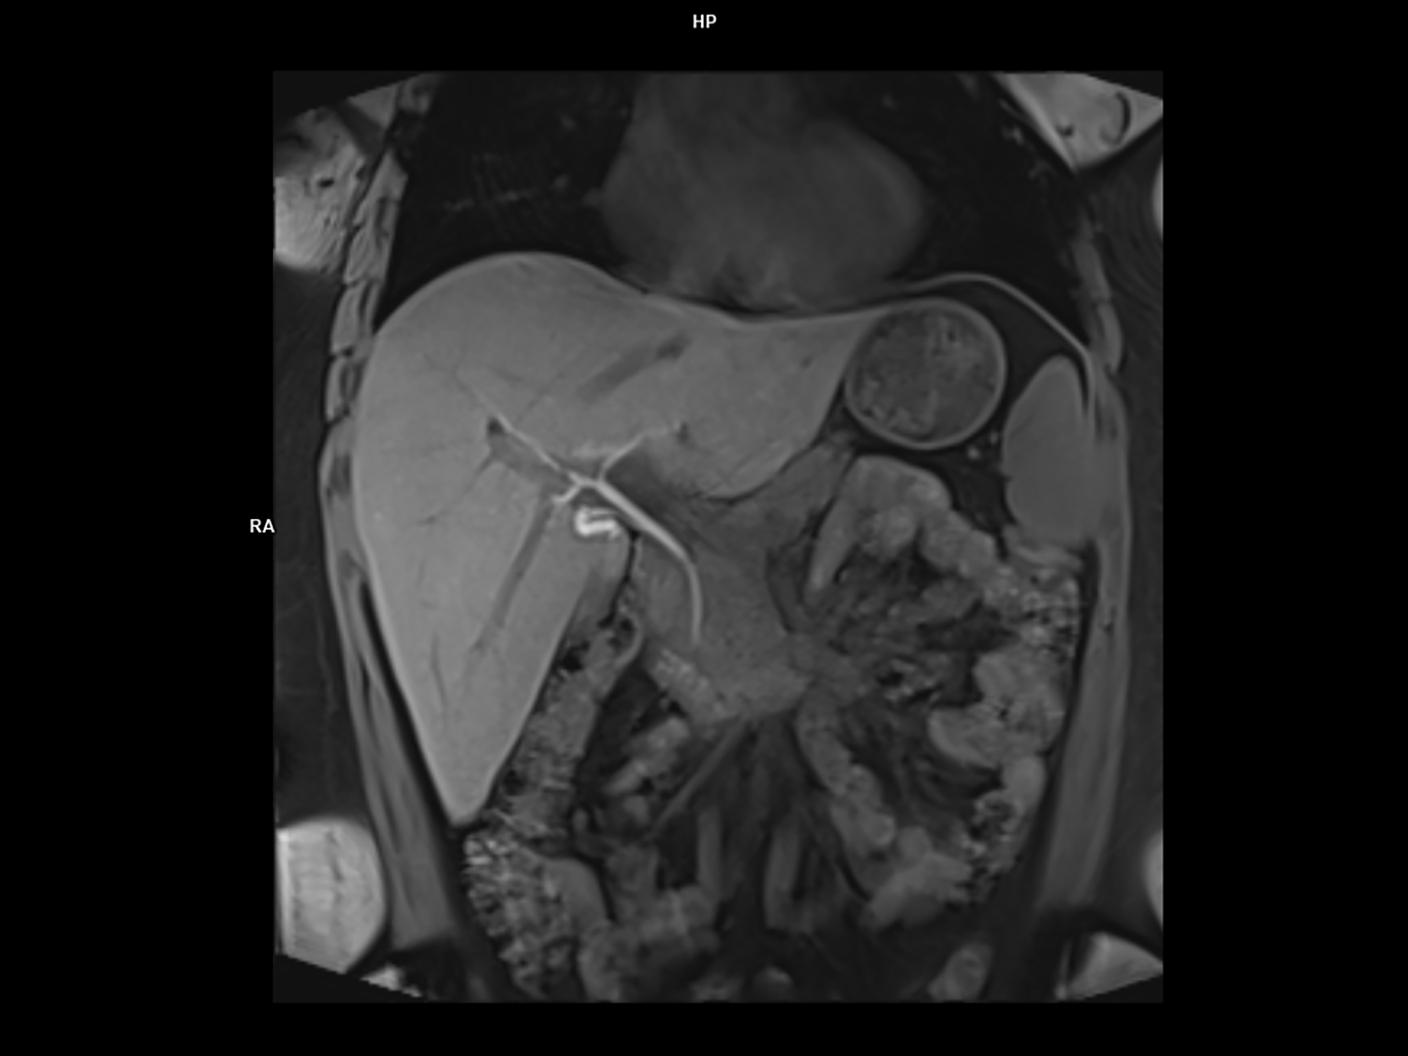

Coronal Vibe Dixon-MAGNETOM Vida

Coronal Vibe Dixon-MAGNETOM Vida/Resolution-320/Aceleration-p4